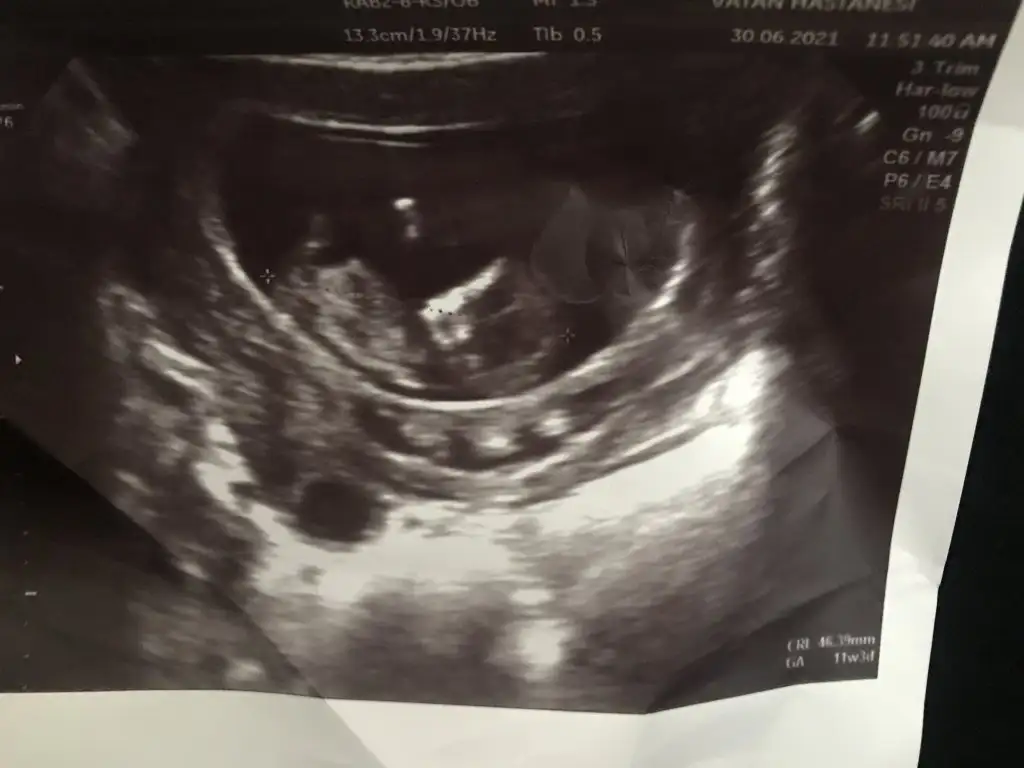

Selamlar kızlar bugün doktor ense kalınlığını ölçtü sata göre 10+5 crl e göre 11+3 üz. Ense kalınlığı 1.2 çıktı normal di mi bu değer? Bir de T tulperde benimkinin cinsiyetini bir de nub a göre değerlendirir misin